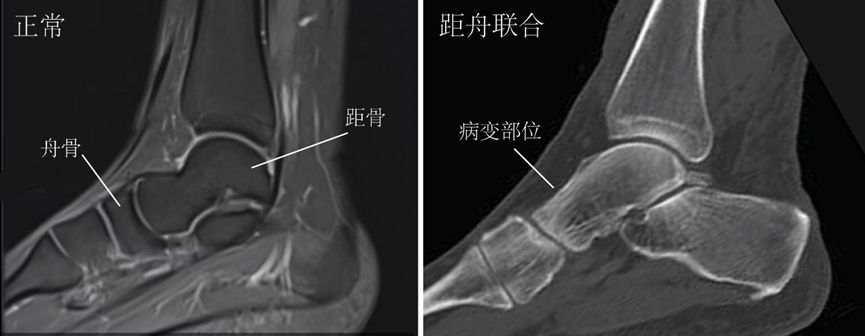

▶距舟联合:发病率相对较低,占跗骨联合患者的1%~2%。

图4:距舟联合的影像学改变